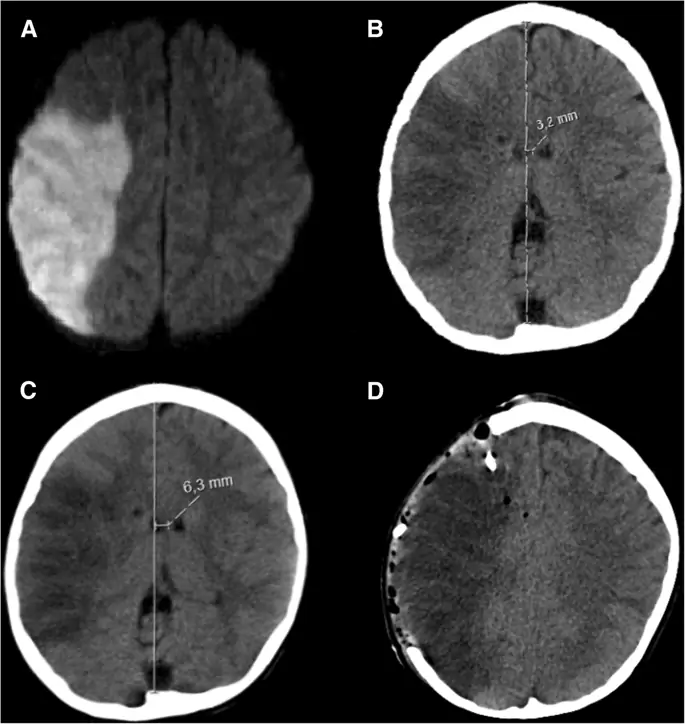

figure10

Педиатрический ишемический инсульт. Типичный пример педиатрического ишемического инсульта у 6-летнего мальчика с серповидно-клеточной анемией: осевая диффузионно-взвешенная последовательность МРТ (а) с повышенным сигналом на правой территории MCA, что указывает на ишемический инфаркт. Осевая компьютерная томография, полученная на 1-й день после начала инсульта (b), показывает демарктированный инфаркт со смещением средней линии 3, 2 мм. Осевая КТ, полученная на 2-й день после начала инсульта (с), выявляет прогрессирующее смещение средней линии на 6, 3 мм, что коррелирует с неврологическим ухудшением. Аксиальная компьютерная томография после гемикраниэктомии и имплантации правого лобного интрапаренхимального зонда ICP (d) с изменением смещения средней линии